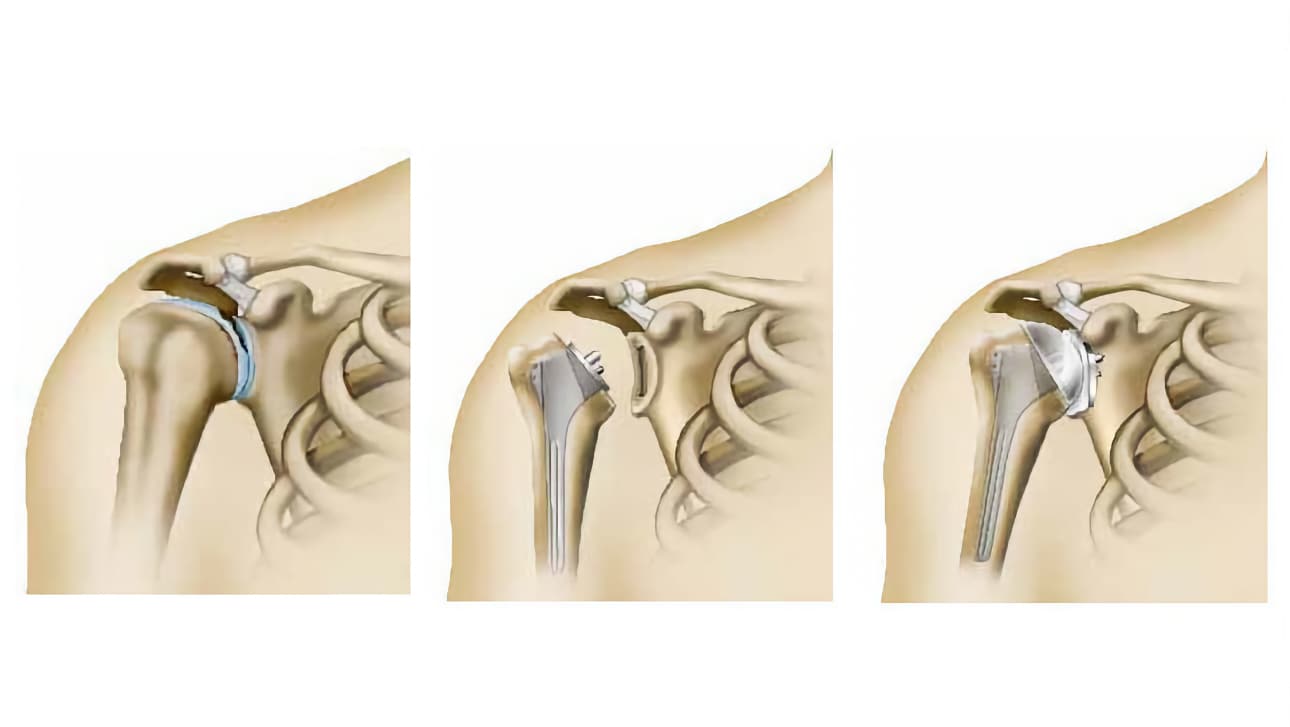

Υπάρχουν πολλές τεχνικές για να το επιτύχει. Ο χειρουργός σας, σας προτείνει αυτή που θεωρεί κατάλληλη για την περίπτωσή σας.